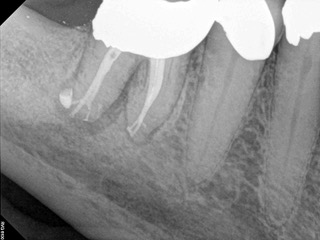

A body of research has emerged in recent years on the management of severe dental pain, exemplified by the diagnosis of an acute apical abscess where drainage cannot be achieved, symptomatic apical periodontitis, or irreversible pulpitis.11 An example of an acute apical abscess is depicted in Figure 1 and Figure 2. These conditions typically represent the most severe discomfort experienced by patients, and consequently, they serve as an excellent model for pain management. Treatment strategies for these issues and other painful conditions should include both definitive treatments for the diagnosed condition as well as adjunctive pharmacologic management.

(2.) The infection was managed with oral antibiotics, root canal therapy, and a combination of ibuprofen and acetaminophen to manage the preoperative and postoperative discomfort.

Figure 2